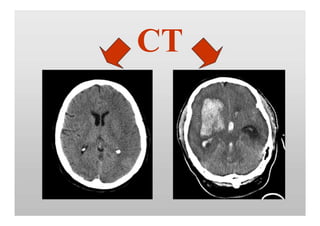

CT

BLUTUNG

KLASSIFIKATION der Blutung

• Hypertensive Blutung (Basalganglien, Pons)

• Blutung unter Antikoagulation

• Parenchymblutung bei Gefäßmalformation

• Subarachnoidalblutung bei Aneurysma

• Sekundär hämorrhagischer Infarkt

• Einblutung in Tumor

Weitere Diagnostik / Therapie in Absprache mit

=> Neurologen, Neurochirurgen, (Neuro-)Radiologen

Blutung: Kriterien für sofortige

Kontaktaufnahme mit NCH

Klinische Kriterien:

Vigilanz-Minderung

Hirndruckzeichen

CT Kriterien:

Raumfordernde Blutung

Mittellinien-Verlagerung

Ventrikeleinbruch / beginnender Hydrocephalus

Blutung in der hinteren Schädelgrube

Subarachnoidalblutung